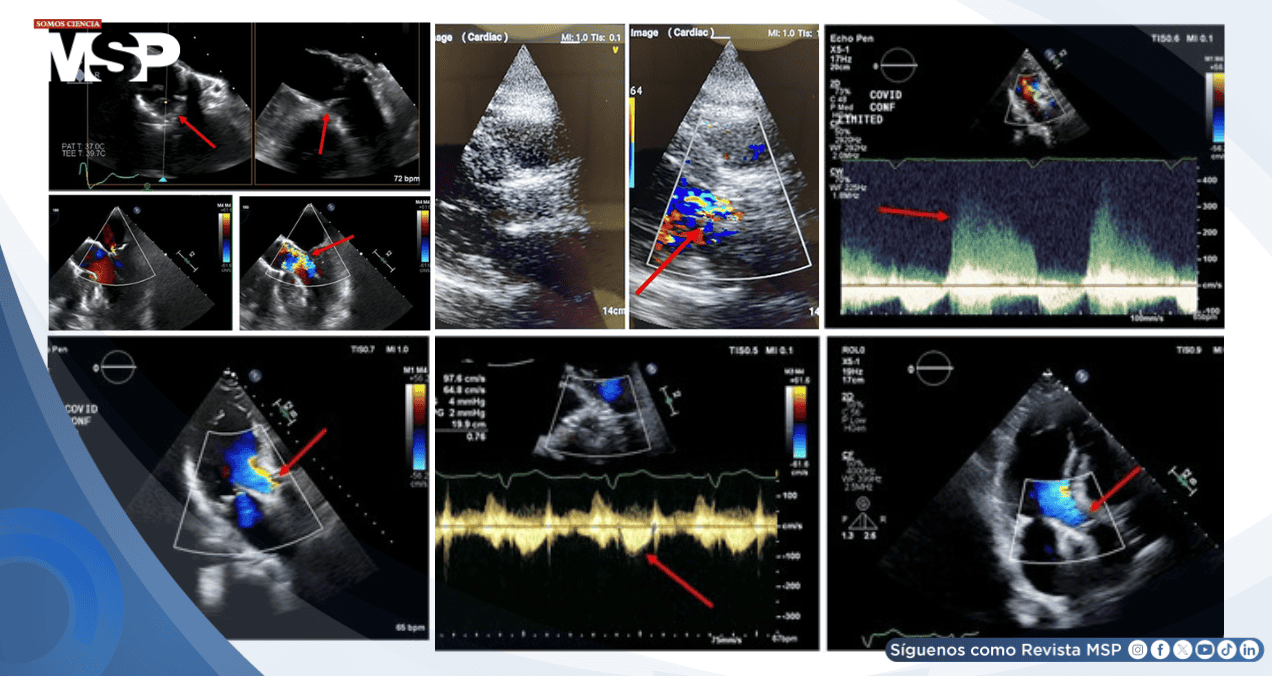

El ecocardiograma transtorácico realizado durante la hospitalización evidenció un flujo diastólico significativo a través de la válvula bioprotésica, hallazgo compatible con regurgitación aórtica severa.

Tres días después, el TEE mostró engrosamiento de las cúspides valvulares, movilidad anormal y un chorro regurgitante excéntrico, confirmando el diagnóstico de trombosis de la válvula bioprotésica con insuficiencia aórtica aguda.